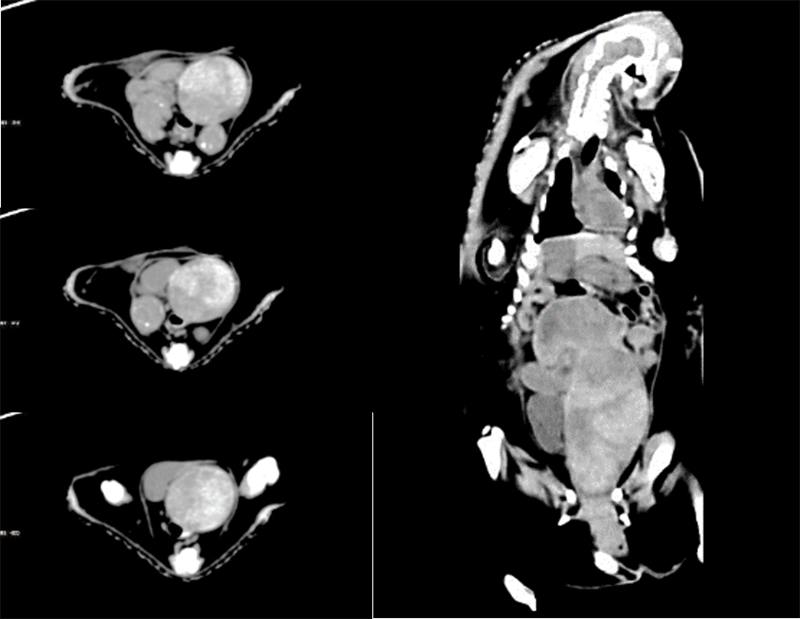

Clinical Gallery